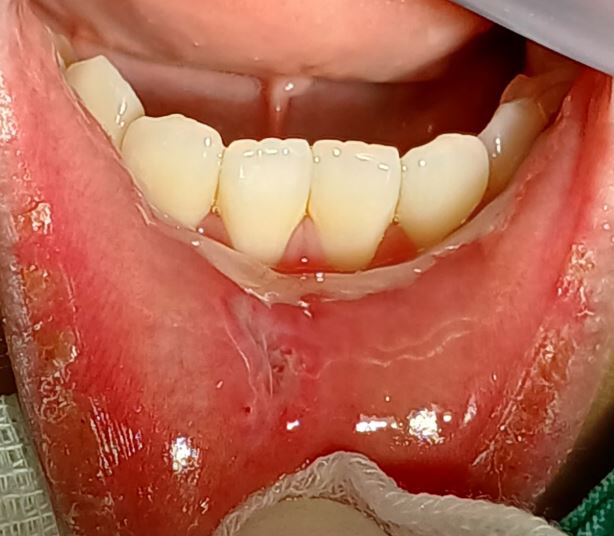

입술 안쪽 점액낭종 제거

입술 안쪽 점액낭종 제거입니다.

구강외과 전문의가 수술합니다.